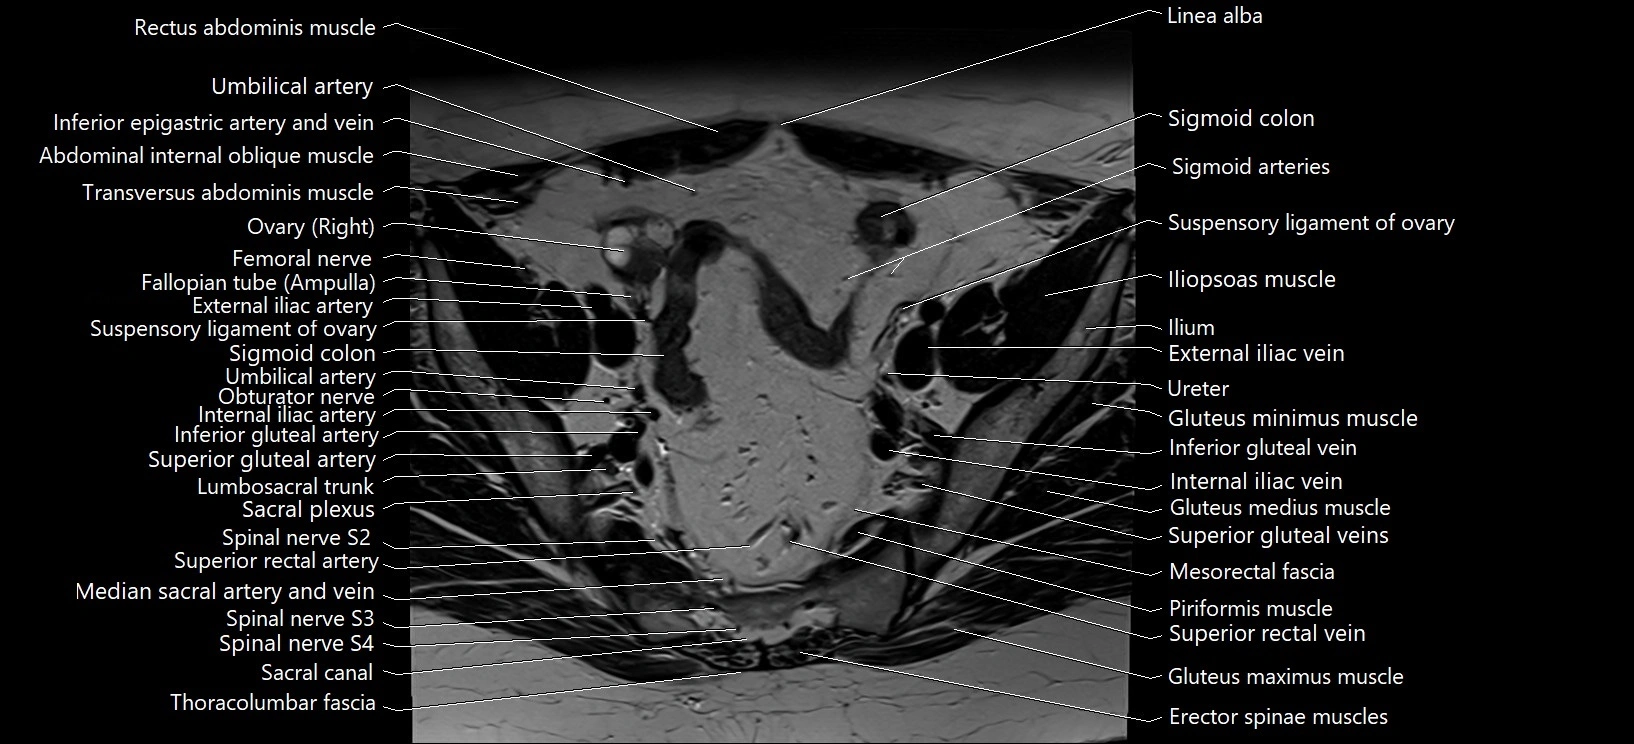

- Erector spinae muscles

- Gluteus maximus muscle

- Gluteus medius muscle

- Gluteus minimus muscle

- Iliopsoas muscle

- Inferior mesenteric artery (IMA)

- Internal iliac vein

- Linea alba

- Lumbosacral trunk

- Mesorectal fascia

- Piriformis muscle

- Sacral plexus

- Sigmoid colon

- Spinal nerve S2

- Spinal nerve S3

- Spinal nerve S4

- Superior gluteal artery

- Superior gluteal veins

- Superior rectal artery

- Superior rectal vein

- Suspensory ligament of ovary

- Transversus abdominis muscle